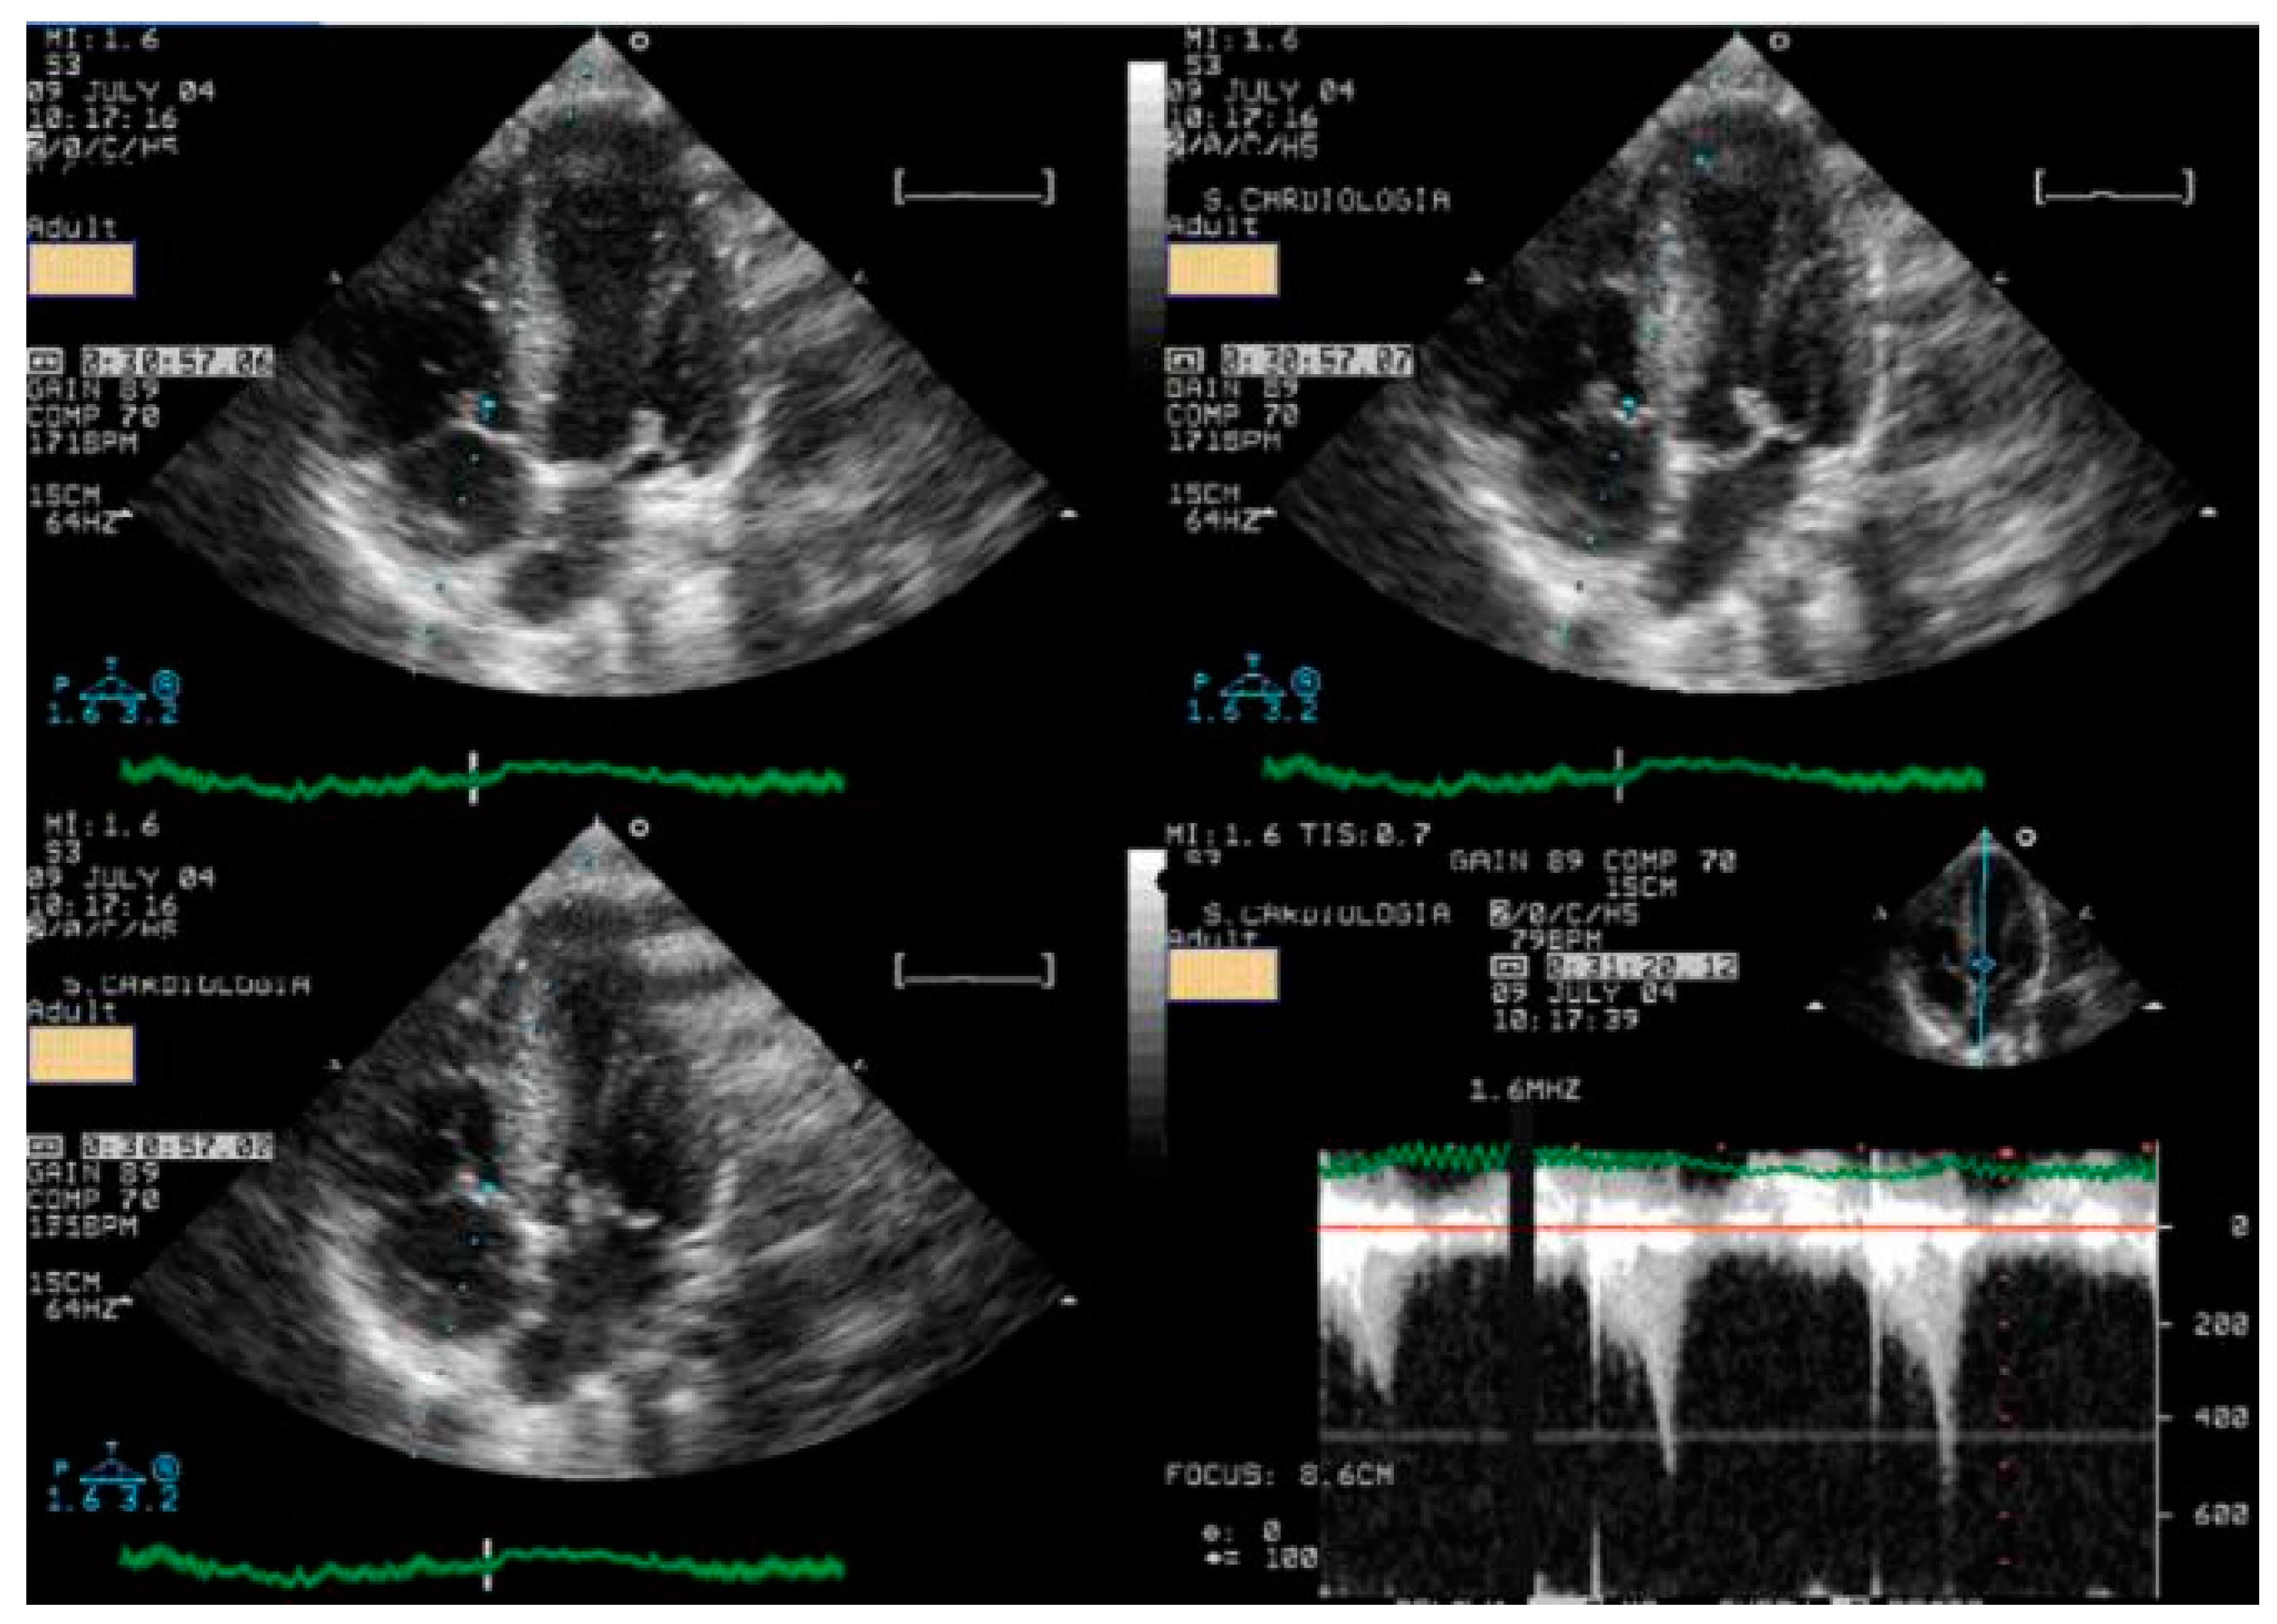

Children underwent treadmill exercise tests guided by symptoms using the standard Bruce protocol [22]. A modified version of the Bruce protocol was utilized to facilitate the assessment of Doppler parameters, providing a simpler evaluation compared to the classical Bruce protocol. Standard twelve-lead electrocardiographic monitoring was conducted, with measurements of ST-segment alterations and any arrhythmias, heart rate, and blood pressure taken at baseline and each stage of the exercise protocol. Before the exercise test, a baseline echocardiogram was performed with the child in the left lateral decubitus position for initial assessment. This involved acquiring 2D and M-mode images in at least four planes: parasternal long- and short-axis and apical four- and two-chamber views (with Doppler parameters evaluated and stored based on clinical requirements). During the exercise test, two-dimensional echocardiographic images were obtained from the parasternal long- and short-axis and apical four- and two-chamber views, with the child in a standing position at rest, during exercise (see Figure 1), at peak exercise, in the immediate post-exercise period, and during recovery [1].

Figure 1.

Image acquisition in the orthostatic position during exercise stress echocardiography using a treadmill for a 17-year-old boy with chest pain related to exercise.

Image acquisition during peak and immediately post-exercise was facilitated using a continuous image-capturing system. Subsequently, frames showcasing optimal image quality and prominent Doppler signs were meticulously chosen in each perspective. The obtained digitized images underwent thorough review and comparison, presented in a digital side-by-side quad-screen format within the echocardiographic equipment. Following the exercise test, as appropriate, patients were promptly positioned in the left lateral decubitus posture, and images were reacquired in identical planes. In circumstances where standing posture was pertinent, such as for detecting and evaluating intraventricular gradients (IVGs) in cases of hypertrophic cardiomyopathy (HCM) or symptomatic children, subjects were instructed to remain standing post-stress test, facilitating echocardiography in this stance [23] (Video S1).